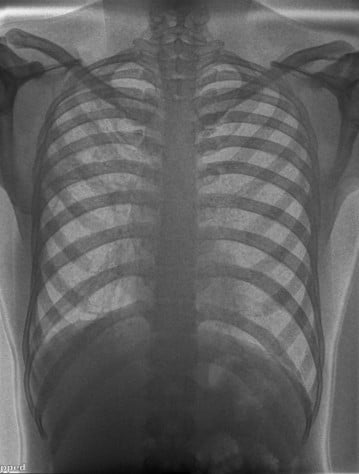

A 22-year-old male presented with a one-month history of dry cough and chest pain. Chest X-ray findings were suggestive of tuberculosis, later confirmed by GeneXpert testing.